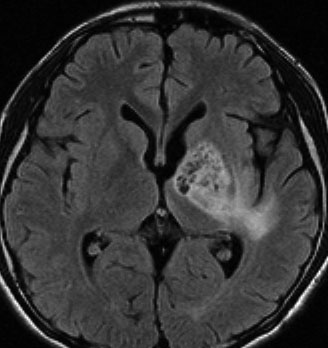

ICE化学療法投与開始から数日で小さくなります

この例は古いので第3脳室開窓術 ETV をしていません。左はICE化学療法前。中央は9日後。右は25日後です。閉塞性水頭症があっても1週間くらいで中脳水道が通って水頭症は改善します。ジャーミノーマであれば,ICE化学療法1コースでかなり縮小するはずです。このような顕著な効果がない時には,逆にジャーミノーマ以外の胚細胞腫瘍が混在していると考えた方がいいでしょう。多くは奇形腫の混在です。